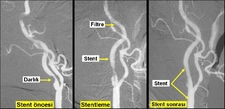

Anjiyo, kalp damarlarının görüntülenmesi için yapılan invaziv bir tanı yöntemidir. Bu işlem, genellikle koroner arter hastalığını değerlendirmek ve tedavi seçeneklerini belirlemek amacıyla gerçekleştirilir. Anjiyo süresi, birçok faktöre bağlı olarak değişiklik gösterebilir. Bu makalede, anjiyo işleminin süresi, aşamaları ve bu süreyi etkileyen faktörler ele alınacaktır. Anjiyo İşleminin AşamalarıAnjiyo işlemi, genel olarak aşağıdaki aşamalardan oluşur:

Anjiyo SüresiAnjiyo işleminin toplam süresi genellikle 30 dakika ile 1 saat arasında değişmektedir. Ancak, işlem süresi aşağıdaki faktörlere bağlı olarak değişebilir: